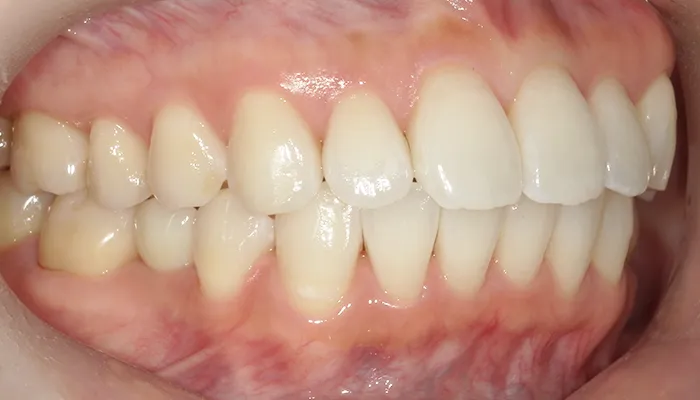

治療後の口腔内写真

術後の口腔内写真

右下5番のインプラントは良好に骨結合し、自然な形態と色調の補綴物を装着しました。

インビザライン矯正により歯列が整い、清掃性・咬合バランスともに改善しました。

ホワイトニングにより歯全体の色調が明るくなり、笑顔の印象が大きく改善しました。

患者様は審美性・機能性ともに大変満足していらっしゃいました。